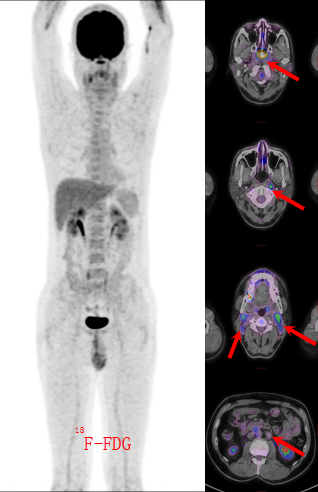

患者入住江西省肿瘤医院鼻咽癌二病区后,先后接受了18F-FDG与18F-CD70双探针PET/CT扫描。

FDG图像上(图1),鼻咽部软组织肿块伴高代谢,同时双颈、腹膜后淋巴结“繁星样”高亮——似乎都在指向“晚期鼻咽癌并广泛转移”。 然而,CD70探针却“语出惊人”:鼻咽病灶浓聚,却有一部分淋巴结仅轻度摄取,甚至阴性(图2)! 核医学科立即发出提示:“双原发可能,建议病理再分型。”

图一